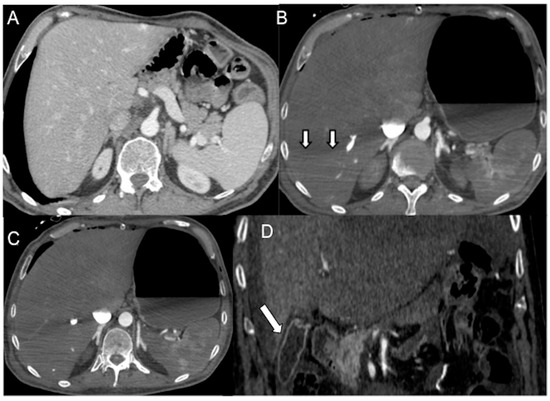

Figure 6.

Distributive septic shock in a 61-year-old male admitted to the emergency department with high fever (39 °C) and sepsis (score for sepsis, qSOFA 3) due to COVID-19 pneumonia (respiratory rate 27/min, systolic blood pressure 75 mmHg, altered mental status). (A,B) Unenhanced chest CT axial images (lung window) show bilateral parenchymal ground-glass opacities due to a diffuse alveolar damage (DAD) pattern; note mild right pneumothorax. (C) CECT axial image in the portal venous phase shows mural thickening (white empty arrow) and mucosal hyperenhancement of the small bowel (white arrow). (D) CECT coronal reconstruction in the portal venous phase shows abnormal wall thickening/enhancement in the partially collapsed transverse colon. Note associated heterogeneous liver enhancement and enhanced thickened pericardium with pericardial effusion (pericarditis).

4.2.3. Bowel (Marked Submucosal Edema and Intense Mucosal Enhancement)

Hypovolemia triggers the sympathetic system, leading to splanchnic vasoconstriction and reduced blood perfusion to the bowel. However, mucosal perfusion is preserved through autoregulation mechanisms that prevent ulceration. This results in prominent mucosal enhancement, which appears greater than the psoas muscle on non-contrast images, and submucosal enhancing edematous wall thickening (bowel wall > 3 mm) [21,27]. Severe hypotension can lead to inadequate oxygen delivery to the organs [22,28]. Reduced perfusion can cause injury to the intramural vessels, resulting in increased capillary permeability and interstitial fluid leakage into the bowel wall and lumen. This leads to decreased fluid reabsorption and eventually ileus, characterized by dilated fluid-filled loops (Figure 6C,D) [19,21,81,82,83,84]. Diffuse bowel ischemia due to vascular occlusion or non-occlusive mesenteric ischemia (NOMI) presents a challenging differential diagnosis. Both conditions can cause bowel wall thickening and luminal distention. However, arterial occlusion-related bowel ischemia does not exhibit diffuse mucosal enhancement or substantial submucosal edema. On the other hand, mesenteric venous occlusion or reperfusion in NOMI may exhibit both of these CT signs [82,83,84].